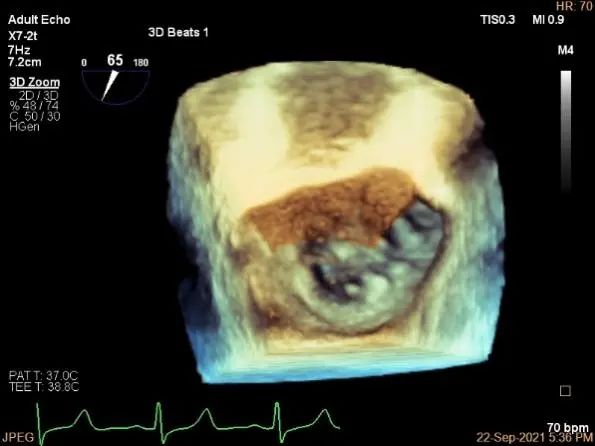

三维评估两个夹子位置

3D-color再次确定未见残余分流

3d确认夹子位置在P1区

3d-color确认残余分流情况